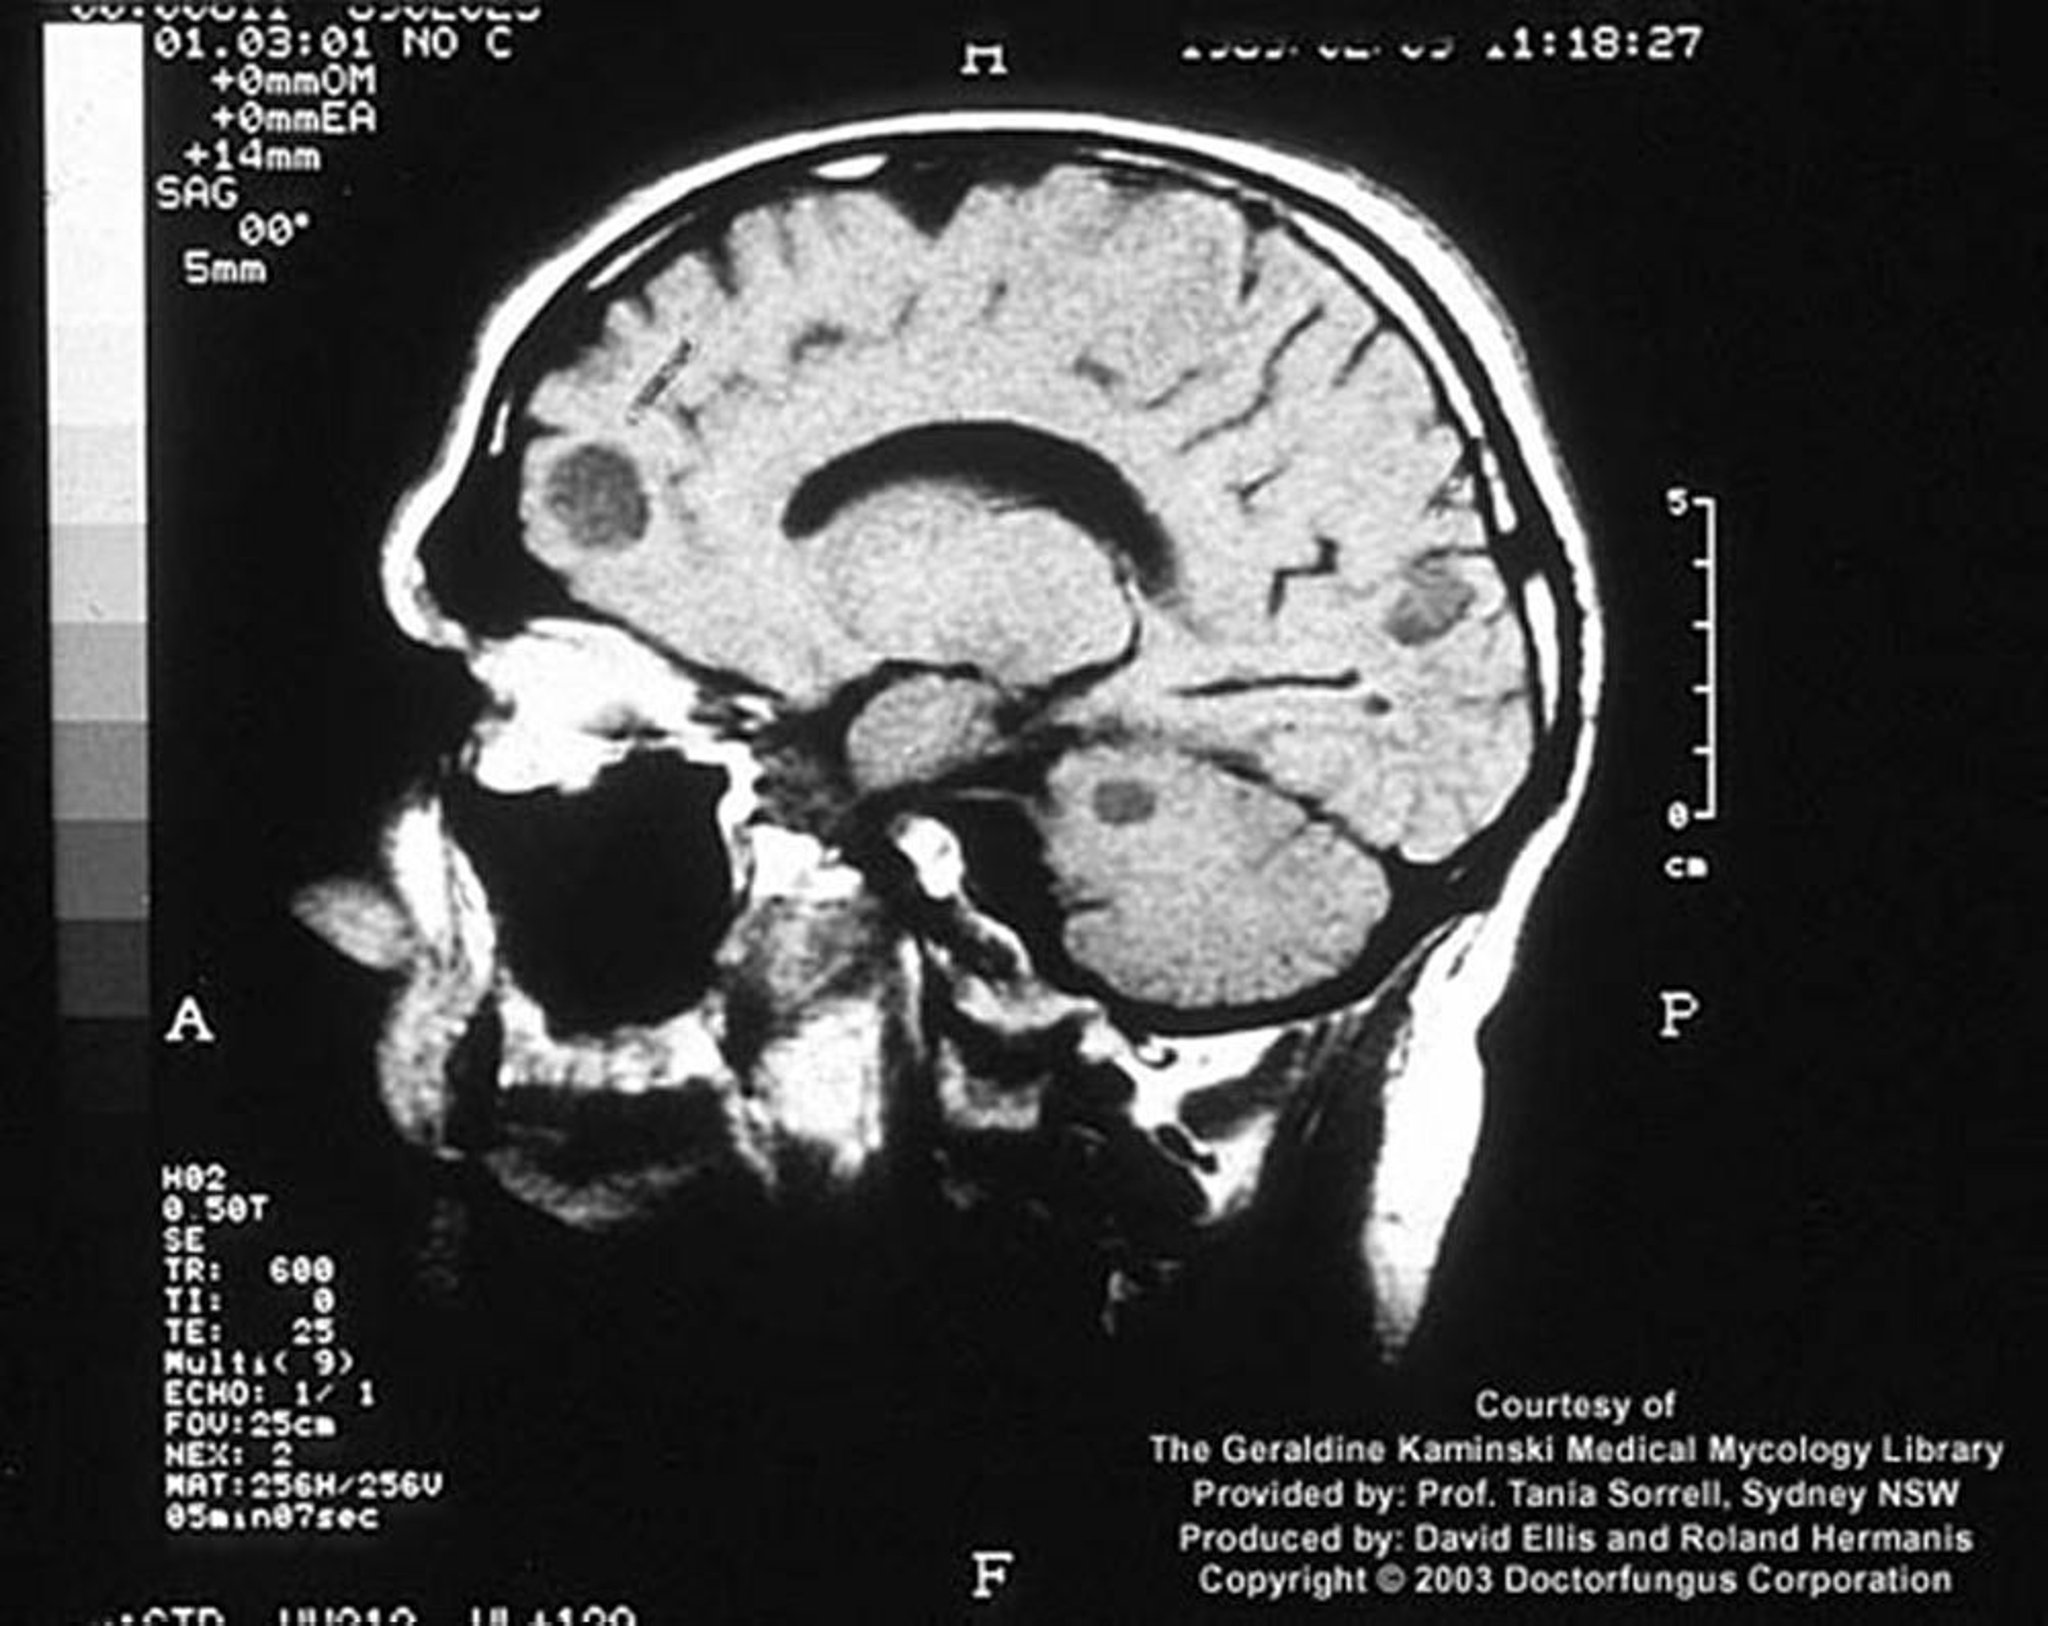

Em um hospedeiro imunocomprometido, a infecção criptocócica pode se manifestar como lesões cerebrais focais denominadas criptococomas.

Imagem cedida por cortesia de www.doctorfungus.org © 2005.